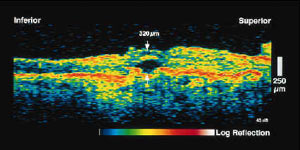

Действие метода основано по аналогии с ультразвуком. Разница в том, что используются не ультразвуковые, а инфракрасные световые волны (843 нм) Разрешающая способность метода – 10 –20 мкм (для сравнения – В-скан – 300мкм) Проникающая способность – несколько мм.